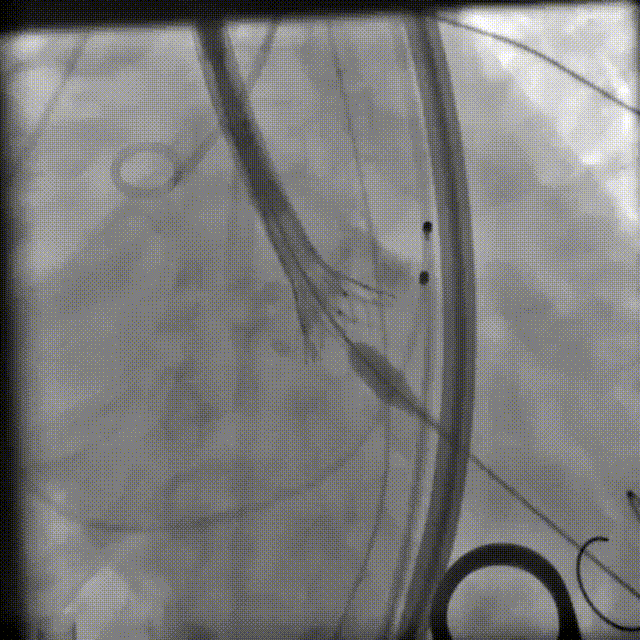

Snare辅助植入TF25号瓣膜,瓣膜可见压缩

-

脱钩后,22mm球囊后扩,瓣膜形态改善